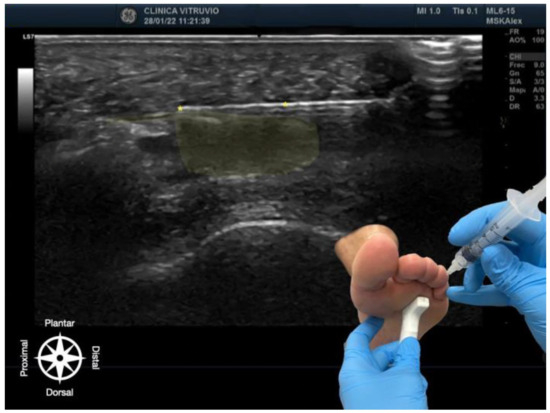

The procedure was performed using high-resolution ultrasound (10–15 MHz linear transducer) under real-time guidance (Figure 1 and Figure 2), following the selective infiltration protocol described by Ruiz Santiago et al. for Morton’s neuroma [3]. Three injections were performed on each anatomical specimen: 1—metatarsophalangeal joint of the third ray (3rd MTP joint), 2—metatarsophalangeal joint of the fourth ray (4th MTP joint), and 3—intermetatarsal space between the third and fourth rays (IM space).

Figure 2. Ultrasound-guided infiltration of the third intermetatarsal space for Morton’s neuroma. The bursa–nerve complex is highlighted in yellow, with the needle following its path, also marked with yellow asterisks (*). In the lower right corner, the plantar approach is shown, illustrating probe and needle positioning. The anatomical orientation diagram indicates the proximal–distal and dorsal–plantar axes.